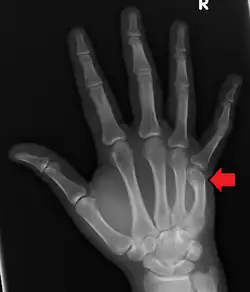

Boxer's fracture of the 5th metacarpal head from punching a wall | |

A boxer's fracture is the break of the fifth metacarpal bone of the hand near the knuckle.[4] Occasionally, it is used to refer to fractures of the fourth metacarpal as well.[1] Symptoms include pain and a depressed knuckle.[2]

Classically, it occurs after a person hits an object with a closed fist.[3] The knuckle is then bent towards the palm of the hand.[3] Diagnosis is generally suspected based on symptoms and confirmed with X-rays.[3]